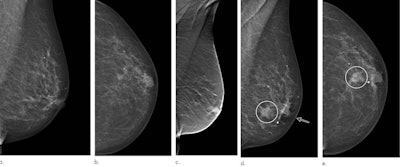

A new study published on 6 April in Radiology indicates the use of digital breast tomosynthesis (DBT) could result in lower interval cancer rates and earlier detection than the use of conventional digital mammography.

The trial was designed to compare one-view DBT with two-view digital mammography (DM) in breast cancer detection for 14,848 women at a clinical practice in Malmö, Sweden, between January 2010 and February 2015. The interval cancer rates and cancer characteristics in the trial were compared with an age-matched contemporary control group, screened with two-view DM at the same center. The screening population for the control group, which consisted of 26,738 screening occasions, saw women screened with standard two-view digital mammography between January 2010 and December 2015.